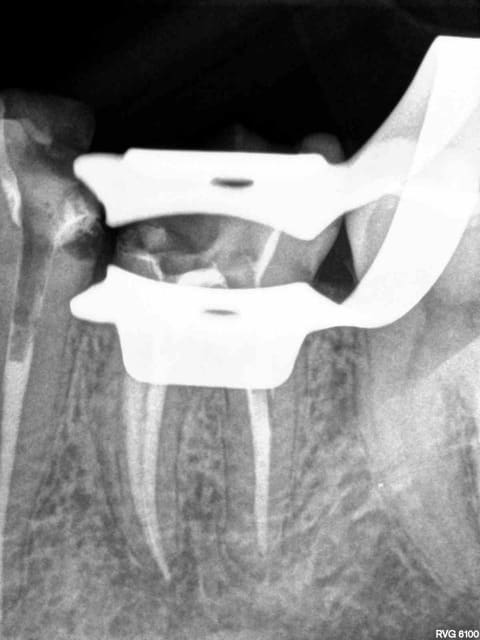

Post de depart !

Honnêtement, la dent est quand même bien niquée !

Fêlure mesiale et distale, le curetage n'est pas complet sur l'arrête restante.

Une couronne, c'est pas une connerie, patient 25-35 on tente l'onlay, patient 45-55, je couronne directement !

C'est une 6 ! 150 kg pression au cm2 !